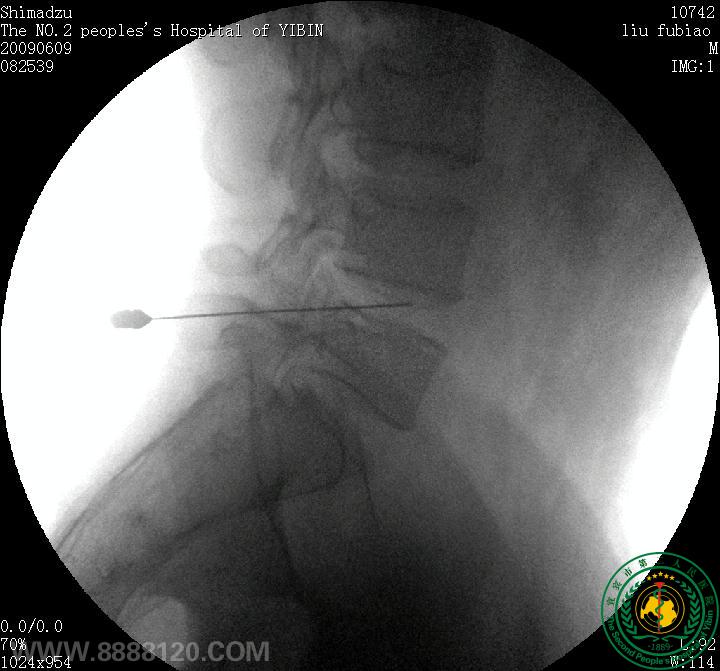

患者为30岁青年男性,经我院CT扫描诊断为腰4/5正中后型椎间盘突出症。经我科李登科、林川两位主治医师术前严格筛查及讨论,认为该患者适合进行臭氧髓核消融,无该手术禁忌症,遂于69日晨830分在经严格消毒后的介入手术室完成了该例手术。术中及术后患者未诉不适。术后于我院CT室复查,见腰4/5椎间盘髓核区臭氧存留。

术前CT                                                                      椎间盘穿刺(1

椎间盘穿刺(2                                                                         术后CT